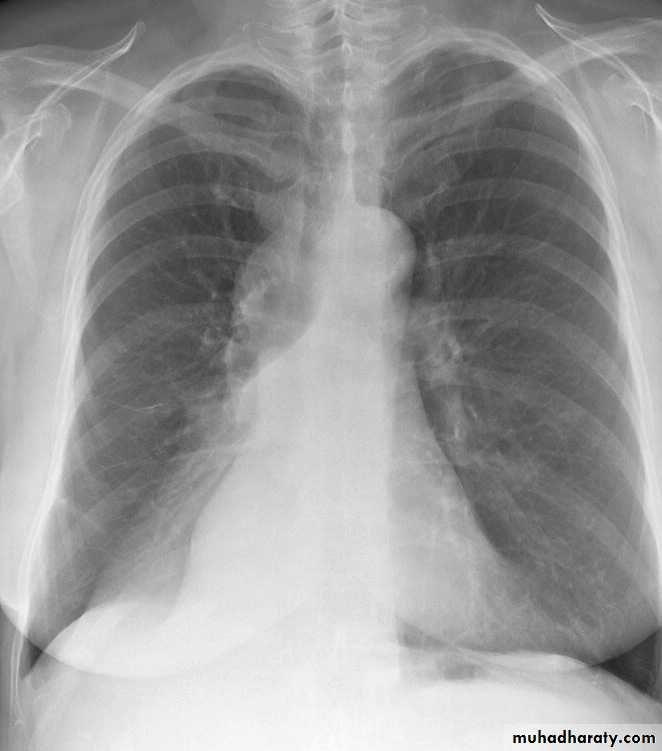

BRONCHOPNEUMONIA

Mycoplasma pneumonia. A 35 year old man presents with nonproductive cough and fever